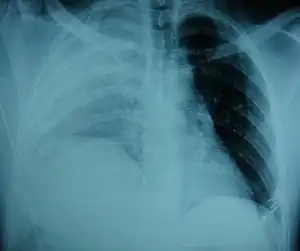

| An X-ray showing a raised diaphragm on the right[1] | |

Physical examinations are not accurate, as there is usually no specific physical sign that can be used to diagnose this condition.[3] Thoracoscopic and laparoscopic methods can be accurate.[12] Chest X-ray is known to be unreliable in diagnosing diaphragmatic rupture;[4] it has low sensitivity and specificity for the injury.[5] Often another injury such as pulmonary contusion masks the injury on the X-ray film.[6] Half the time, initial X-rays are normal; in most of those that are not, hemothorax or pneumothorax is present.[4] A nasogastric tube from the stomach may appear on the film in the chest cavity; this sign is pathognomonic for diaphragmatic rupture, but it is rare.[4] The X-ray is better able to detect the injury when taken from the back with the person upright, but this is not usually possible because the person is usually not stable enough; thus it is usually taken from the front with the person lying supine.[5] Positive pressure ventilation helps keep the abdominal organs from herniating into the chest cavity, but this also can prevent the injury from being discovered on an X-ray.[4]

Between 50 and 80% of diaphragmatic ruptures occur on the left side.[5] It is possible that the liver, which is situated in the right upper quadrant of the abdomen, cushions the diaphragm.[6] However, injuries occurring on the left side are also easier to detect in X-ray films.[4] Half of diaphragmatic ruptures that occur on the right side are associated with liver injury.[5] Injuries occurring on the right are associated with a higher rate of death and more numerous and serious accompanying injuries.[10] Bilateral diaphragmatic rupture, which occurs in 1–2% of ruptures, is associated with a much higher death rate (mortality) than injuries that occur on just one side.[5]